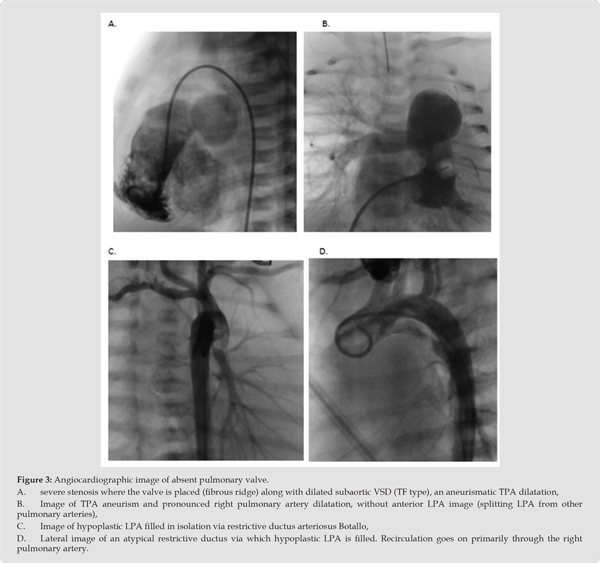

Consequently, they had RVH with suspicion of non-compaction right ventricular cardiomyopathy, more so in patient 4 than in patient 2 (Figure 1A-1D. – patient 2 and Figure 2A-2D-patient 4). Anomaly of ductus arteriosus is suspected in both of patients; in patient 2, a small, restrictive anomalous duct, through which only LPA is supplied, and which is separated from TPA (Figure 3A-3D - patient 2), in patient 4 there is an atypical, wide, tortuous arterial duct through which it enters the TPA, and then through the deficient PV into the RV. Massive insufficiency behind the trunk of the pulmonary artery towards the right ventricle is shown, and then the right ventricle with severe non-compaction cardiomyopathy (Figure 4A-4D - patient 4). In the other two patients, the ductus was not noted in the foetal cardiological examination. Interestingly, all pregnant women had problems during pregnancy; two had gestational diabetes mellitus and arterial hypertension, one had foetal hydrops and cystic hygroma (termination of previous pregnancy at 14 weeks), and one had a previous spontaneous abortion of unexplained aetiology. There is no information on any drug therapy during pregnancy.

In the postnatal diagnosis, all patients had dilatation of the right atrium, insufficiency of the tricuspid valve of varying degrees, dilatation and hypertrophy of the right ventricle, and clear changes in the defective pulmonary valve, which was the cause of severe stenosis in three patients (1,2,3), with a gradient of 60-90 mmHg (Figure 1D, patient 1), and all of them simultaneously had severe insufficiency in the same level of degree II-III, and in patient 4 only severe insufficiency dominates without registered stenosis (Figure 2C, pat. 4)). We reliably found pathological DB in three patients (2,3,4), with the fact that one duct was constricted and directed into the hypoplastic left PA that was separated from the right (Pat. 2) (Figure 3B,C & D, Pat. 2) in the frame of the TF type.

One DA was aneurismatic dilated (Pat. 3), and one was atypically tortuous and wide (Figure 4, Pat. 4)). A ductal anomaly should also be suspected in the first patient (Pat. 1) who was born as a premature child, but it was not diagnostically verified in the period until it theoretically could have closed delayed (3 months after delivery), but a complete absence of the ductus is also possible because it is the socalled TF type of APVS. In addition to the aneurysmal expansion of the TPA, all patients also had marked dilatation of the RPA, and only one had extremely wide both branches of the pulmonary artery (patient 3). We note that as many as three patients had hypoplasia of the left branch of the pulmonary artery (patients 1, 2, 4) (Figures 3 & 4), and patient 2 had extreme hypoplasia of the LPA, which filled through the restrictive DB, and was initially completely separated from the RPA. In patient 3, in whom VSD was mentioned prenatally, we did not find it postnatally, and two patients (pat. 1,2) had right-sided anomalies with subaortic VSD. We did not use the term TF anywhere with certainty because we believe that the basic characteristic of TF is a significantly smaller pulmonary artery than the aorta, while our patients with VSD (pat. 1 and 2) had a significantly wider PA than the aorta. The mean pulmonary artery pressure (mPA) in one patient (pat. 1) was 31 mmHg (measured at the age of 11 months), and the other patients had mPA below 25 mmHg. (pat. 2,3,4).

Special attention deserves the latest reports from the literature regarding the assumption that a special role in the development of the described anomalies is played by the anomaly of the ductus arteriosus. As early as 2002, Yeager discussed the prenatal role of the arterial duct in the development of APVS. In 2014, Quereshi described two patients with tetralogy of Fallot who developed APVS, probably because they did not have a Botallo’s duct., in the phenotypic expression of the defect with the right aortic arch and retroesophageal left subclavian artery, but without a vascular ring. He concludes that every APVS that has a VSD does not have a ductus (TF type), and children with APVS that is not called an isolated form (no VSD) have DB. However, if the TF type of APVS has a ductus, it supplies only the left pulmonary artery that is discontinuous with TPA. This is exactly how we can describe our patient no. 2; tetralogy type of APVS (has a VSD), but also has a DB, which, however, supplies only the left branch of the pulmonary artery, which is discontinuous from the pulmonary trunk and is hypoplastic.